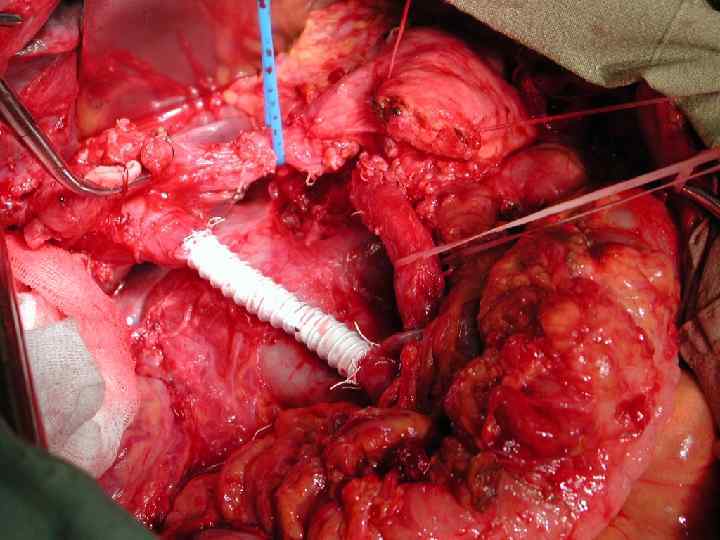

Инвазия чревного ствола и общей печеночной артерии

Резекция чревного ствола и общей печёночной артерии при выполнении ДСРПЖ Вид резекции Циркулярная резекция чревного ствола Всего Число больных с пластикой 4 без пластики 11 15

Верхняя мезентерикография после резекции чревного ствола с ушиванием обоих концов сосуда наглухо. Кровоснабжение печени осуществляется через гастродуоденальную артерию